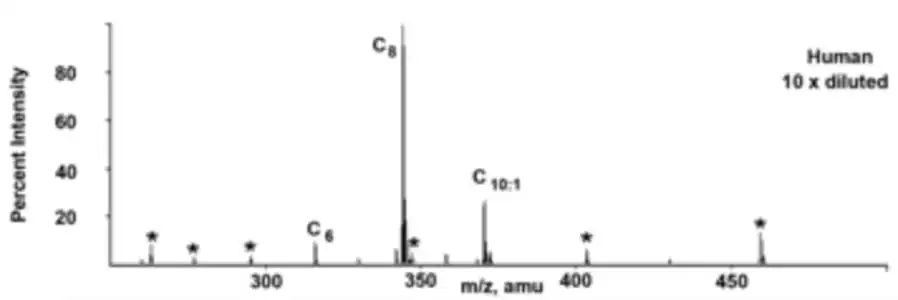

Acylcarnitine profile of an individual with MCADD, showing characteristic elevation of octanoylcarnitine (C8)

Acylcarnitine profile of an individual with MCADD, showing characteristic elevation of octanoylcarnitine (C8)

In areas with expanded newborn screening using tandem mass spectrometry (MS/MS), MCADD is usually detected shortly after birth, by the analysis of blood spots collected on filter paper. Acylcarnitine profiles with MS/MS will show a very characteristic pattern of elevated hexanoylcarnitine (C6), octanoylcarnitine (C8), decanoylcarnitine (C10) or decenoylcarnitine (C10:1), with C8 being greater than C6 and C10. Secondary carnitine deficiency is sometimes seen with MCADD, and in these cases, acylcarnitine profiles may not be informative.[3] Urine organic acid analysis by gas chromatography-mass spectrometry (GC-MS) will show a pattern of dicarboxylic aciduria with low levels of ketones. Traces of acylglycine species may also be detected. Asymptomatic individuals may have normal biochemical lab results. For these individuals, targeted analysis of acylglycine species by GC-MS, specifically hexanoylglycine and suberylglycine can be diagnostic.[3][5] After biochemical suspicion of MCADD, molecular genetic analysis of ACADM can be used to confirm the diagnosis.[6] The analysis of MCAD activity in cultured fibroblasts can also be used for diagnosis.[3]